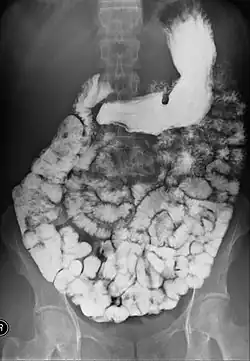

| Upper gastrointestinal series | |

Normal barium swallow fluoroscopic image, showing the ingested barium sulfate being induced down the oesophagus by peristalsis. | |